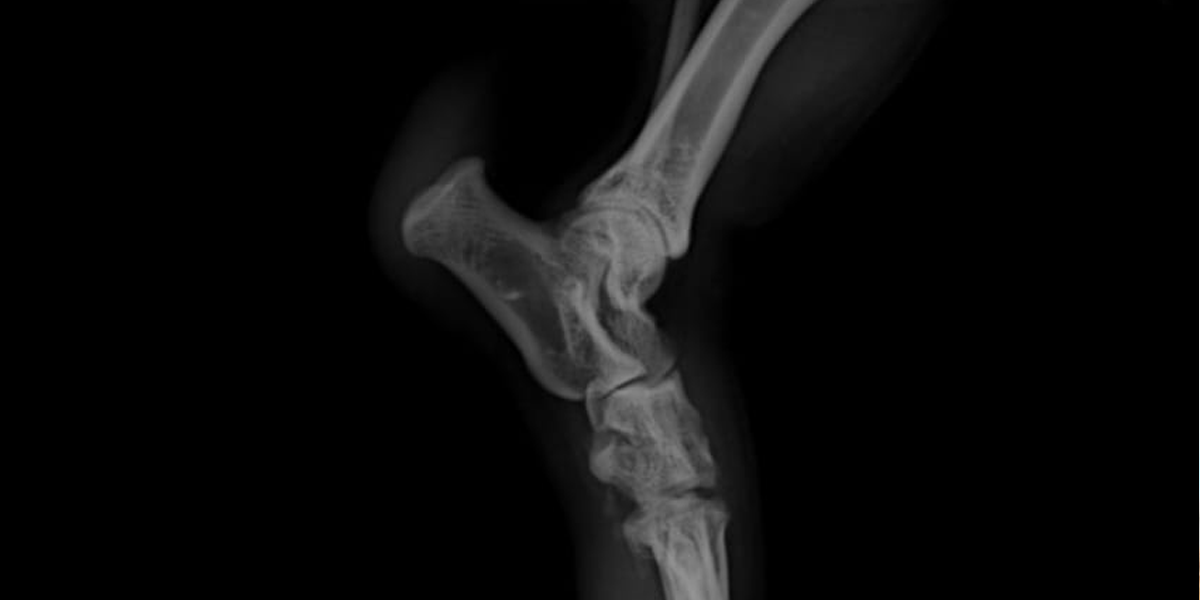

Advanced digital X-ray technology is a cornerstone in veterinary diagnostics, providing high-resolution images of an animal’s internal structures.

This sophisticated imaging tool allows veterinarians to quickly and accurately diagnose a range of conditions from bone fractures to internal organ anomalies. Unlike traditional X-ray systems, advanced digital X-rays produce clearer images and can be easily adjusted for better viewing without the need for multiple exposures. This technology not only reduces the stress on the animal by shortening the time spent under examination but also enhances the ability of veterinarians to make precise diagnoses and monitor treatment progress. The ability to share digital images electronically with specialists further improves the speed and quality of veterinary care.

This sophisticated imaging tool allows veterinarians to quickly and accurately diagnose a range of conditions from bone fractures to internal organ anomalies. Unlike traditional X-ray systems, advanced digital X-rays produce clearer images and can be easily adjusted for better viewing without the need for multiple exposures. This technology not only reduces the stress on the animal by shortening the time spent under examination but also enhances the ability of veterinarians to make precise diagnoses and monitor treatment progress. The ability to share digital images electronically with specialists further improves the speed and quality of veterinary care.